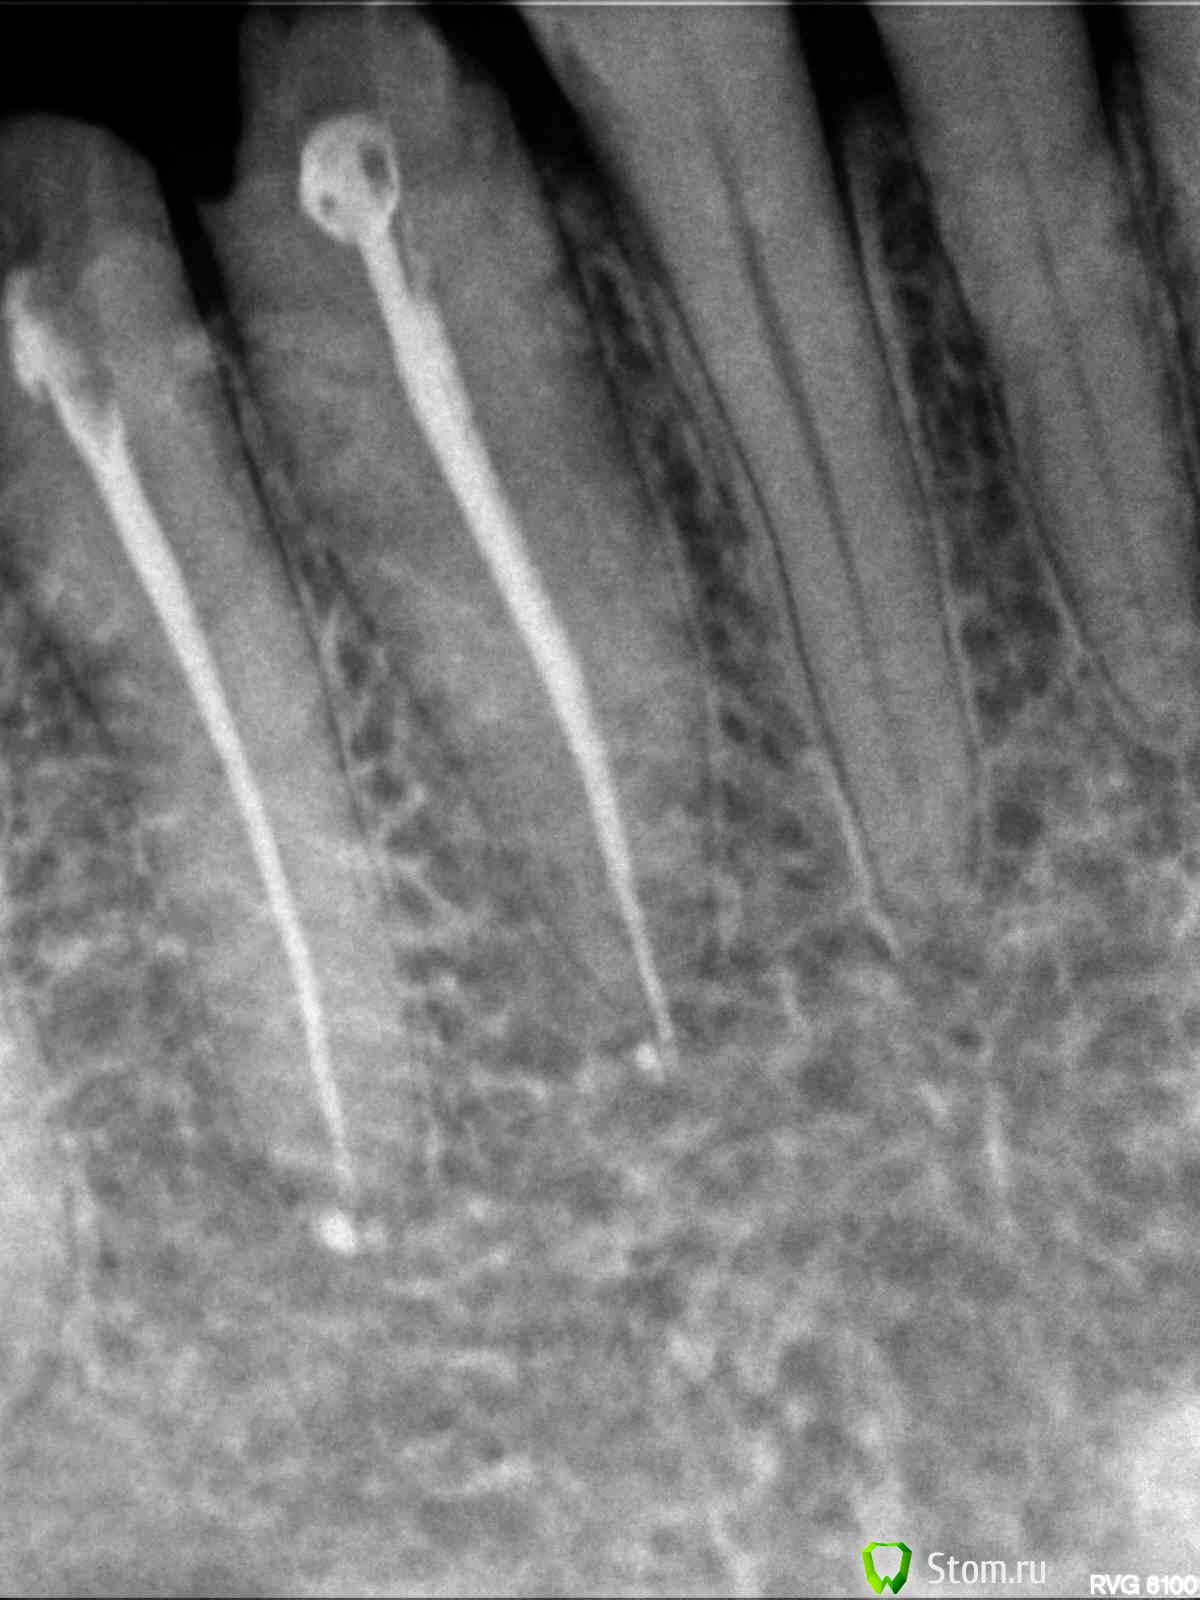

evm Опубликовано 26 апреля, 2012 Поделиться Опубликовано 26 апреля, 2012 Здравствуйте! Проблема: на живых 3-ке, 4-ке и 5-ке внизу справа стояла металлопластмасса (мост полуразрушенный, травмировал десну). Хотела менять осенью, но, поскольку стали появляться ночные ноющие боли (терпимые, но с Метрогилом-Дента), решила не тянуть. 28 марта под анестезией депульпировали все три зуба и запломбировали. Когда пломбировали, в 5-ке чувствовала боль и потом было больно по ней стучать. 10 апреля должна была уже начать протезирование (металлокер. на штифтах). 3 и 4 молчали, а 5-ка все время мозжила и к 10 апреля поддала жару- воспалился лимфоузел и боль усилилась, а также появился болезненный участок рядом с корнем. Канал открыли, положили лекарство под временную пломбу, через три дня - повторили. Терапевт все время убеждала, что с зубом полный порядок. Другой врач сказала: или аллергия, или периодонтит на маленьком учаске (в узкой щели), где тяжело достать (это мой вольный пересказ ее слов). Боль если и утихала, то очень медленно и зуб чувствовала всегда. Через три с половиной недели (22 апреля) взбесилась 4-ка, больно было толкать языком и болела больше, чем 5 (возможно, из-за замерзших накануне ног). Поскольку первый врач считал, что у меня все вылечено, пошла ко второму. Та сделала укол (антибиотик плюс ультракаин, на лидокаин была раньше алергия - крапивница по всему лицу, как герпес), вспомнили мы про физлечение, и в своей поликлинике стала делать дэнос и атерм.УВЧ. Опять пошла алергия, сначала думала - на инъекцию, а теперь думаю, может быть и на ток - пузыри кучно в месте контакта с электродом, а на лидокаин до этого - по всему лицу. Пока все отменили. Зубы периодически о себе напоминают. По 4-ке стучать больнее, чем по 5-ке. 4-ку не открывали. Аллергия (тогда почему 3-ка молчит?) или хр.периодонтит? На снимке видно, что у 5-ки пломб.материал вышел за верхушку, но, скорее всего мозжащая (а иногда пульсирующая, но спать дающая) боль не из-за этого? Ссылка на комментарий

Magdalena Опубликовано 29 апреля, 2012 Поделиться Опубликовано 29 апреля, 2012 Если подвела антисептическая обработка каналов, что Вы предлагаете делать мне? Перелечивать не только 5 зуб, но и 4. Видимо, диагностика по снимкам затруднена, пока нет патологии в виде гранулем и кистОбычные прицельные снимки - двухплоскостные, по ним не всегда видно локализацию воспалительного процесса, ход и количество корневых каналов. Поэтому для более точной диагностики существует компьютерная 3Д - томография (трехмерная), на ней зуб можно "покрутить" и посмотреть со всех сторон, а также в поперечном срезе (это помогает определить кол-во и ход каналов). Ссылка на комментарий